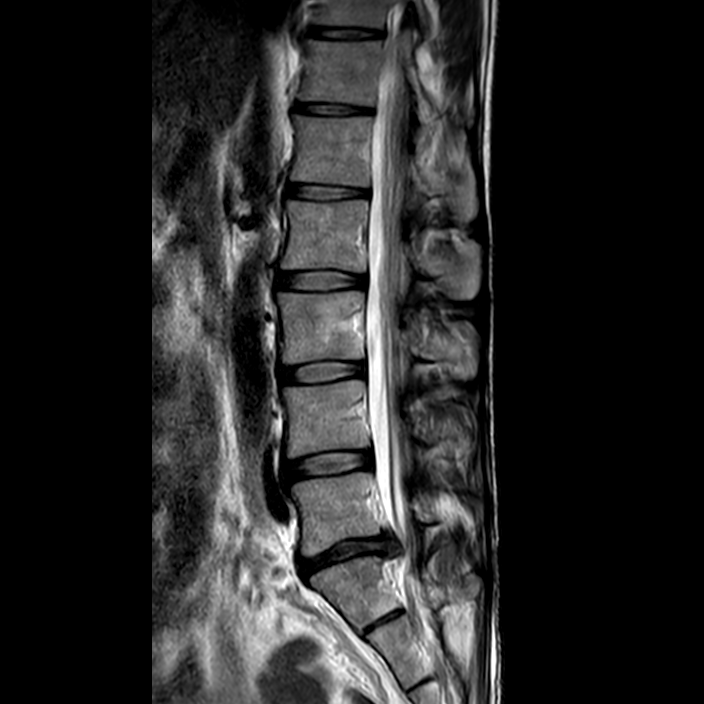

In the results was a text file with the following: “Isolated L5-SI disc disease: L5/S1: Reduced hydration with a right paracentral protrusion effacing the lateral recess and impinging on the traversing right S1 root.”

The image below shows the disk at the base of the spine with the protrusion into the spinal nerve area.

Now I had a confirmed diagnosis, I forwarded this to my osteopath, and it confirmed what he told me on my first visit as the most likely cause.

At the end of June, I had a letter from Poole Hospital with a telephone appointment with the spinal consultant I spoke with them in July and after discussing the pain and issues and the consultant agreed that I needed an MRI scan to confirm the cause of the pain and from the symptoms, it appeared likely to be an L5 / S1 disk problem.

In September, I spoke to the spinal consultant again and she explained the MRI results, and the disk was not a candidate for surgery so I should continue with the pregabalin tablets and the physio and osteopath exercises. I was told that normally this sort of disk problem goes away within 12 weeks for most people but for some, it can go on for much longer.